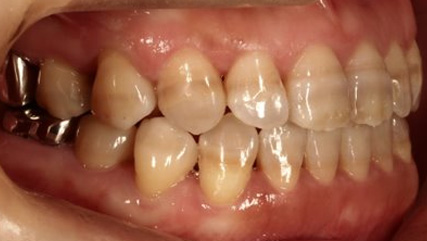

治療前

治療終了前

乱ぐい歯、でこぼこがとても酷い状態になります。歯が前後的に重なってしまっている、八重歯になっているなどがこのジャンルに入ります。

顎の大きさと歯の大きさのギャップが大きく、時には歯を抜かないと矯正治療ができない場合もあります。当院では治療期間が長くなるが抜かない治療方針など、一つの治療プランだけでなく、さまざまな可能性の治療方針を説明させて頂くよう心掛けております。こういった考え方はインフォームド・チョイスと言われ近年大切にされている考え方と言われております。